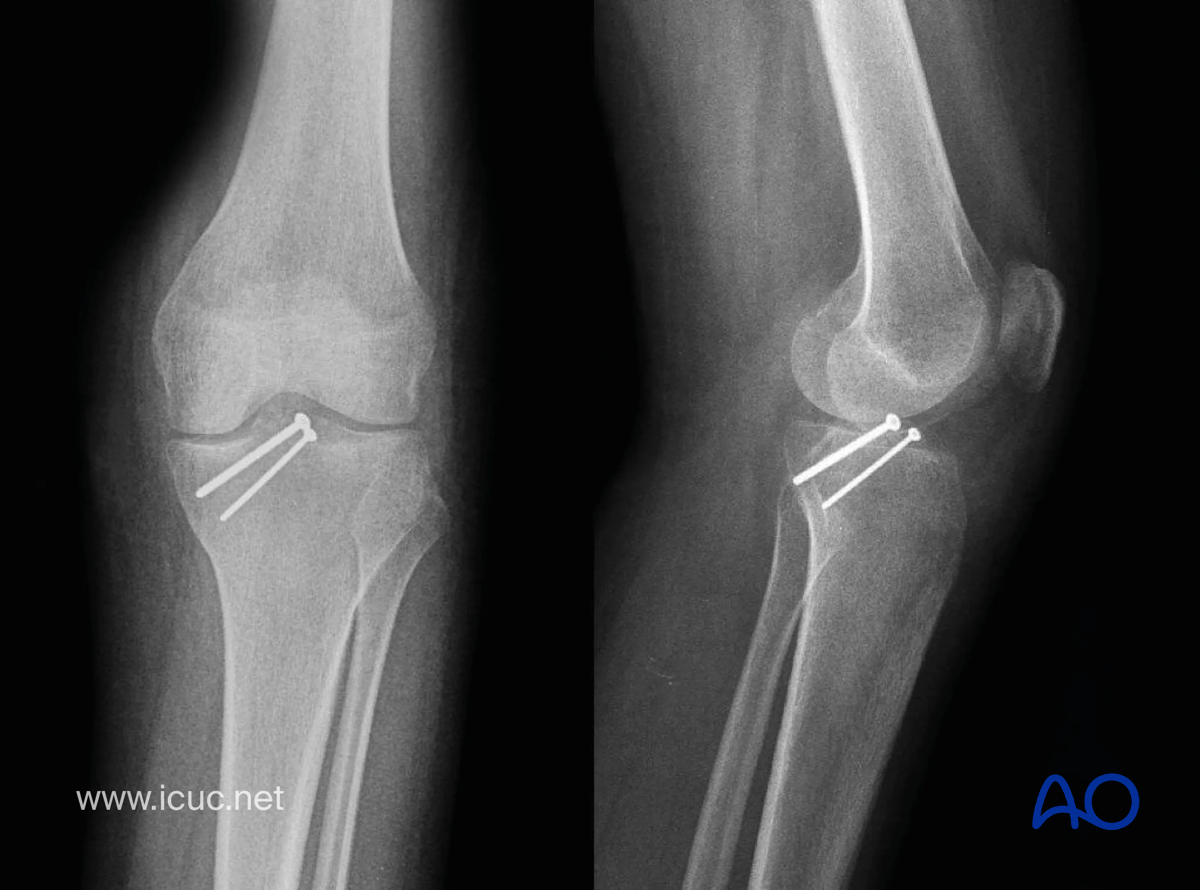

Four-week X-ray showing reduction of the spine.

Avulsion of tibial spine – four-week X-ray showing reduction of the spine